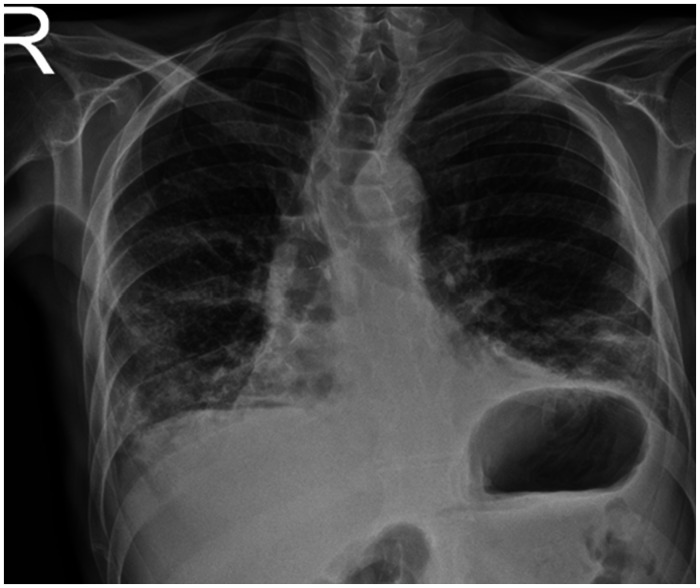

囊性纤维化患者可考虑肺移植。尽管与其他患者相比,这些患者可能经历更成功的结果和生存率,但可能出现各种并发症。特别是,感染性并发症和脓毒性死亡在囊性纤维化患者中可能比其他肺移植适应症更普遍。考虑到所有这些因素,识别和处理该患者组术后可能出现的并发症至关重要。在这篇文章中,我们按时间顺序介绍了一例因囊性纤维化而接受肺移植的患者在移植后发生的多种危及生命的并发症,并对其处理进行了讨论。

Cystic fibrosis patients may be considered for lung transplantation. Although these patients may experience more successful outcomes and survival rates compared to others, various complications can arise. In particular, infectious complications and septic deaths may be more prevalent in cystic fibrosis patients compared to other lung transplant indications. Considering all these factors, recognizing and managing complications that may arise during the postoperative period in this patient group are of critical importance. In this article, multiple life-threatening complications occurring in the post-transplant period in a patient who underwent lung transplantation due to cystic fibrosis are chronologically presented, and their management is discussed.